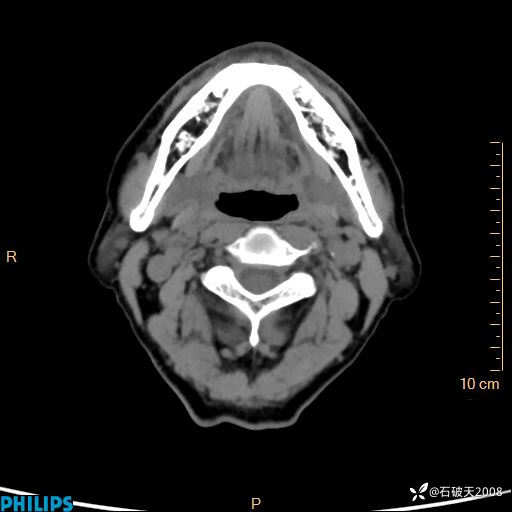

静脉期